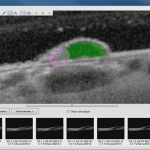

CornAI

L’application de suivi des caractéristiques morphologiques des cellules endotheliales dans le contexte des greffes de cornée